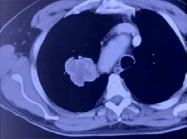

经CT检查发现肿瘤血运非常丰富易出血。所以复大的医生先给他做了一个穿刺活检,明确肿瘤的性质。

在第一次做穿刺的时候,老人家出现了咳血。复大肿瘤医院的专家团队考虑到病人属于容易出血的体质,从安全的角度来看,微波消融比冷冻消融对血运丰富的肿瘤更合适,更安全。因为,微波可以产生高达150度的高温,它可以在烧死肿瘤的同时凝固血管,就不会出血了。另外,就算穿刺过程中有出血,也能通过高温及时止血,这就是微波消融的优势所在。

牛立志教授用2.0的微波针,穿刺到肿瘤中心,十分钟就将肿瘤消融掉了。消融后,可以看到肿瘤被烧死,同时看到毛玻璃样改变。